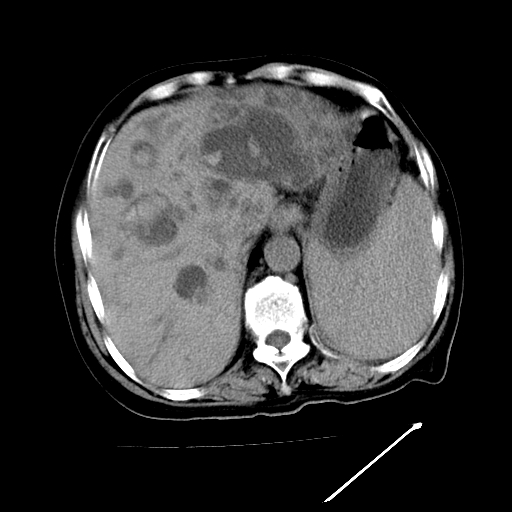

以下是引用卜一在2009-4-7 5:06:00的发言:[br]左右肝内胆管结石伴扩张合并胆系感染;不除外胆管细胞癌可能。支持! [br] [br]

以下是引用随光逐影在2009-4-7 8:21:00的发言:[br]肝内外胆管多发性结石并肝内外胆管扩张;胆系感染。